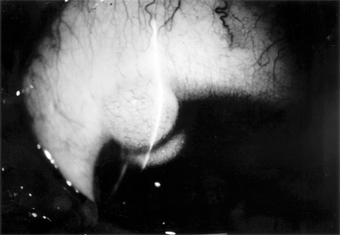

Chapter 5: Conjunctiva IV. CONJUNCTIVAL TUMORS PRIMARY BENIGN TUMORS OF THE CONJUNCTIVA Nevus (Figure 5-26) One-third of melanocytic nevi of the conjunctiva lack pigment. Over half have cystic epithelial inclusions that can be seen clinically. Histologically, conjunctival nevi are composed of nests or sheets of nevus cells. Conjunctival nevi, like other nevi, rarely become malignant. Many are excised because they are disfiguring. Pigmented conjunctival nevi must be distinguished from primary acquired melanosis of the conjunctiva. The latter occurs later in life (after the third decade), is usually unilateral, tends to wax and wane in degree of pigmentation, and, depending on the degree of cellular atypia, has a risk of becoming malignant ranging from nil to 90%. Papilloma Conjunctival papillomas occur in two forms: infectious papillomas, associated with a papovavirus, occurs in children and young adults, especially in the inferior fornix and near the medial canthus (Figure 5-27). The other type arises from a broad base, often near the limbus, in older adults and may be indistinguishable from conjunctival intraepithelial neoplasia. A biopsy may be required to establish the diagnosis. Granulomatous Inflammation Granulomatous inflammation occurs around foreign bodies, around extravasated sebaceous material in chalazia, and in association with diseases such as coccidioidomycosis and sarcoidosis. These inflammatory foci may form elevated plaques or nodules in the skin or the conjunctiva of the eyelids. Dermoid Tumor (Figure 5-28) This congenital tumor appears as a smooth, rounded, yellow elevated mass, frequently with hairs protruding. A dermoid tumor may remain quiescent, though it can increase in size. Removal is indicated only if cosmetic deformity is significant or if vision is impaired or threatened. Limbal dermoids and dermolipomas are most often isolated lesions, but occasionally they may be part of such syndromes as oculoauriculovertebral dysplasia (Goldenhar's syndrome). Dermolipoma Dermolipoma is a common congenital tumor that usually appears as a smoothly rounded growth in the upper temporal quadrant of the bulbar conjunctiva near the lateral canthus. Treatment is usually not indicated, but at least partial removal may be indicated if the growth is enlarging or is cosmetically disfiguring. Posterior dissection must be undertaken with extreme care (if at all) since this lesion is frequently continuous with orbital fat; orbital derangement may cause scarring and complications far more serious than the original lesion. Lymphoma & Lymphoid Hyperplasia These are conjunctival lesions that may appear in adults without evidence of systemic disease or associated with systemic lymphosarcoma or various blood dyscrasias. The clinical appearance of benign lymphoid hyperplasia and malignant lymphoma can be similar; therefore, biopsy is essential to establish a diagnosis. Since many of these lymphoid tumors may involve the orbit, an magnetic resonance imaging (MRI) or computed tomography (CT) scan may be required to determine the true extent of the tumor. Treatment of both benign and malignant lesions is best accomplished with radiotherapy. Angioma Conjunctival angiomas may occur as isolated, circumscribed capillary hemangiomas or as more diffuse vascular tumors, often associated with a more extensive lid or orbital capillary or cavernous hemangioma. Hemangiomas should be distinguished from telangiectases involving conjunctival capillaries. Telangiectatic conjunctival vessels may occur as isolated lesions or may be associated with systemic vascular hamartomas in Rendu-Osler-Weber disease or in ataxia-telangiectasia (Louis-Bar syndrome). Pyogenic granulomas are a variety of capillary hemangiomas. They frequently occur on the palpebral conjunctiva over chalazia or in an area of recent surgery. In Kaposi's sarcoma associated with AIDS, red-blue vascular nodules may first become apparent in the conjunctiva. They are associated with a herpesvirus. Radiotherapy is the most effective treatment. Bacillary angiomatosis is another proliferative vascular lesion that may appear similar to Kaposi's sarcoma. It is due to infection with gram-negative bacteria of the genus Bartonella-B henselae from cats in patients with AIDS and B quintana from body lice in low-income homeless individuals. These tumors respond to antibiotic therapy. PRIMARY MALIGNANT TUMORS OF THE BULBAR CONJUNCTIVA Carcinoma Carcinoma of the conjunctiva arises most frequently at the limbus in the area of the palpebral fissure and less often in nonexposed areas of the conjunctiva. Some of these tumors may resemble pterygia. Most have a gelatinous surface; sometimes, abnormal keratinization of the epithelium produces leukoplakia. Growth is slow, and deep invasion and metastases are extremely rare; therefore, complete excision is effective treatment. Recurrences are common if the lesion is incompletely excised; treatment consists of reexcision. The use of cryotherapy may help to prevent recurrences. Conjunctival dysplasia, also called atypical epithelial dysplasia, is a benign condition that occurs as an isolated lesion or sometimes over pterygia and pingueculae and can resemble carcinoma in situ clinically and even histologically. The term conjunctival intraepithelial neoplasia can be applied to all neoplastic lesions from dysplasia to carcinoma that are confined to the epithelium. Excisional biopsy will establish a diagnosis and result in cure of most of these lesions. Malignant Melanoma Malignant melanomas of the conjunctiva are rare. Most arise from areas of primary acquired melanosis; some arise from conjunctival nevi; a few apparently arise de novo from normal conjunctiva. Some are melanotic; others are heavily pigmented (Figure 5-29). Many tumors can be locally excised. More radical surgery (eg, exenteration of the orbit) does not usually improve the prognosis. The use of cryotherapy after excision of melanotic tumors may help to prevent recurrences. PREVIOUS | NEXT Page: 1 | 2 | 3 | 4 | 5 | 6 | 7 | 8 | 9 | 10 | 11 | 12 | 13 | 14 10.1036/1535-8860.ch5 |